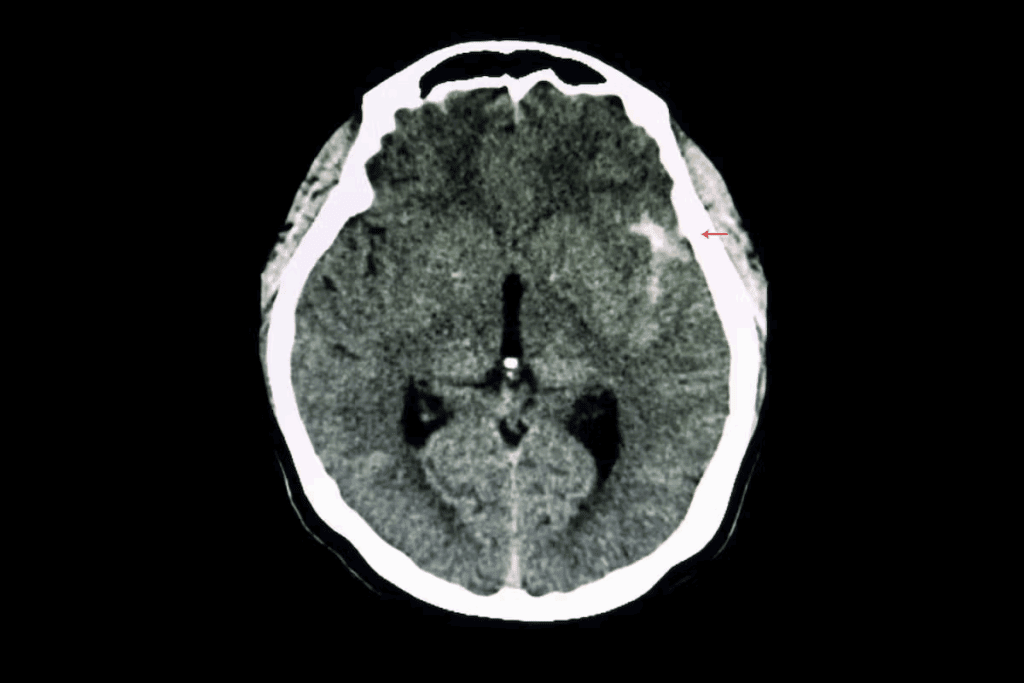

A brain aneurysm is a bulge in a blood vessel in the brain. It happens when the blood vessel wall is weak. Brain aneurysms can rupture, leading to bleeding in the brain, known as a subarachnoid hemorrhage, which is a life-threatening condition requiring immediate medical attention.

How Aneurysms Form in Cerebral Arteries

Aneurysms in cerebral arteries happen when the artery wall weakens. This can be due to genetics, high blood pressure, or atherosclerosis. The weakened area bulges, forming a sac-like structure that can rupture.